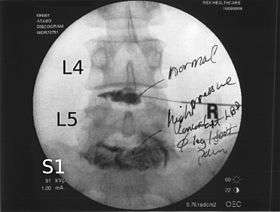

Lumbar provocative discography showing a degenerated disc, L5-S1 with normal disc L4-L5 | |

Lumbar provocative discography (also referred to as "discography" or discogram) is an invasive diagnostic procedure for evaluation for intervertebral disc pathology. It is usually reserved for persons with persistent, severe low back pain (LBP) who have abnormal spaces between vertebrae on magnetic resonance imaging (MRI), where other diagnostic tests have failed to reveal clear confirmation of a suspected disc as the source of pain, and surgical intervention is being considered.

Needles are inserted through the back into the disc near the suspect area, guided by fluoroscopic imaging. Fluid is then injected to pressurize the disc, and any pain responses are recorded.

This is repeated in random order for the various discs, without the patient knowing which disc is pressurized. This can be used to detect patients who may be exaggerating their symptoms, or to assess their pain response and hence their suitability for recovery from possible surgery (often a Discectomy).

A contrast agent is introduced, and after the procedure a CT scan identifies leakage from the discs to identify any spinal disc herniation.